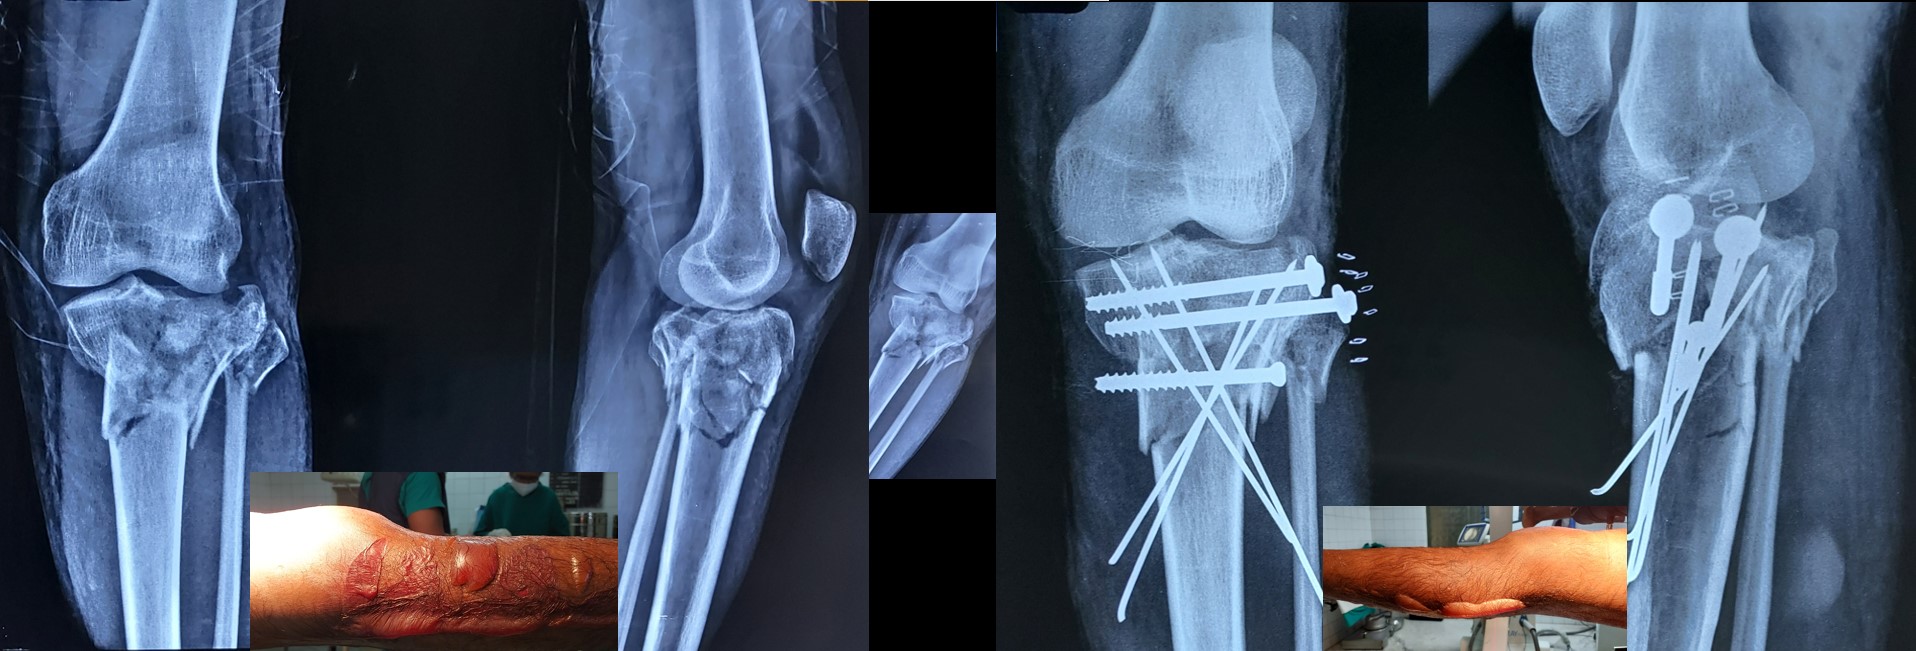

CRPP ( Closed Reduction Percutaneous Pinning )

• No skin incision is required, and fracture heals faster than open surgeries as there is no iatrogenic soft tissue damage or disturbance to the fracture hematoma.

• No implants projecting outside the skin and hence painless adjacent joint movement is possible immediately after CRPP.

• PCCS (Percutaneous Cannulated Cancellous Screws) can be added to CRPP, when interfragmentary compression is a must.

• It can be applied safely in fractures, where ORIF (Open Reduction Internal Fixation ) cannot be performed or postponed due to impending soft tissue complications.